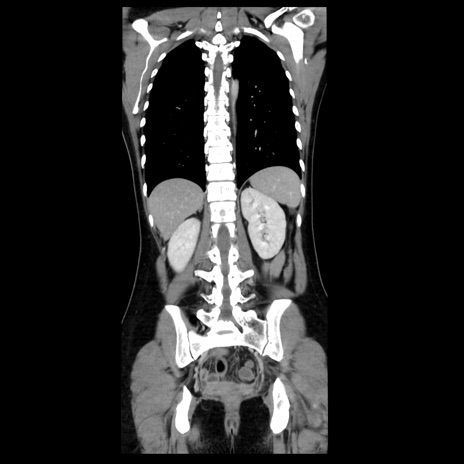

症例39(冠状断像)

【症例】40歳代女性

【主訴】上下腹部痛

【現病歴】2日目から下腹部痛あり。夜間は痛みで眠れなかった。昨日より上腹部痛と下痢が出現。臥位で痛みは軽快したため、休んでいた。本日になって臥位でも立位でも痛みが強くなってきたため救急要請。

【既往歴】子宮内膜症

【身体所見】部:平坦・軟、左上下腹部に圧痛あり、反跳痛あり。

【データ】WBC 21800、CRP 26.78

CT